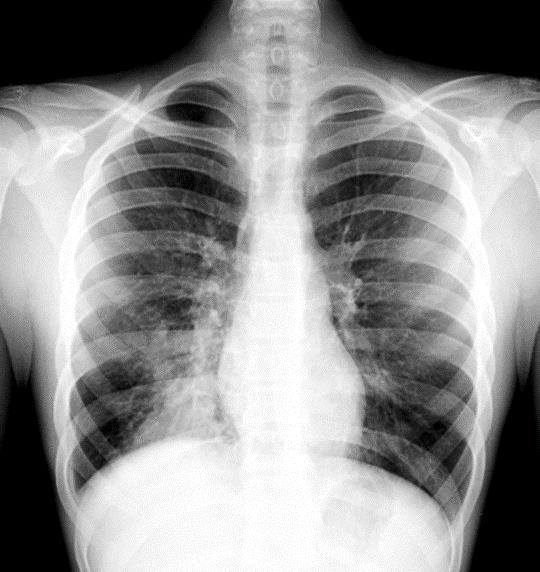

Homem, 27 anos, sem comorbidades prévias conhecidas, iniciou quadro de disfagia alta há dois meses, episódios de febre ocasional não aferida e perda de 4 Kg, a qual relacionou à dificuldade de se alimentar. Conta ainda que nos últimos cinco dias vem sentindo discreta dispneia ao caminhar e dor torácica ventilatório dependente em hemitórax direito. A febre tornou-se mais intensa e diária, atualmente aferida em 38,5 a 39°C, além de tosse produtiva com secreção amarelada e sem hemoptise. Ao exame físico, regular estado geral, presença de estertores crepitantes em base pulmonar direita. Frequência respiratória de 25 incursões por minuto, saturação de oxigênio 95%, frequência cardíaca 98 batimentos por minuto, pressão arterial 110/80 mmHg e perfusão preservada. Oroscopia, abdome, neurológico e de membros inferiores sem alterações dignas de nota. Foram solicitados os exames de investigação descritos abaixo (Figuras 6 e 7):

-----------------------------------------Figura 6. Radiografia de tórax simples póstero anterior